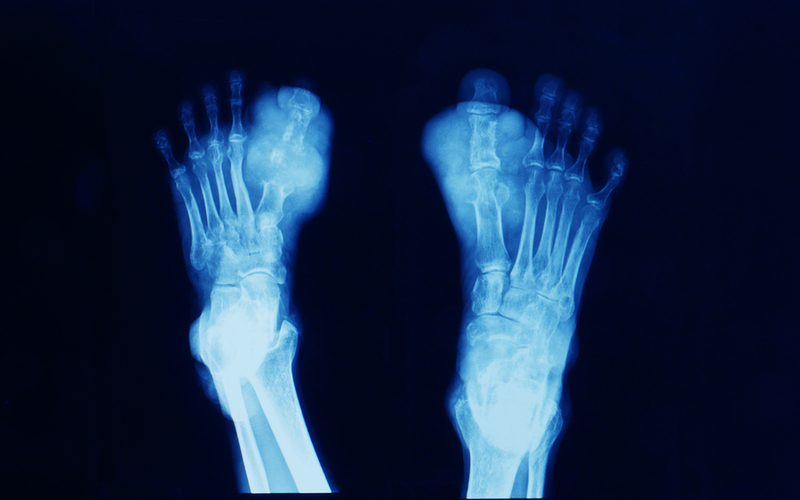

Gout is a very common condition. It is caused by deposits of crystals of a substance called uric acid (also known as urate) in the joints, which leads to inflammation. Periods of time when gout symptoms appear are called flares. Flares can be unpredictable and debilitating, developing over a few hours and causing severe pain in the joints.